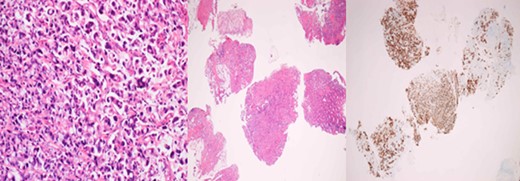

A 43-year-old female, 10 weeks postpartum, underwent colonoscopy for bleeding per rectum showing a bulky tumour (Fig. 1) in the rectum at 5 cm. Histologically poorly differentiated adenocarcinoma of the rectum (Fig. 2) T3N1Mo. Underwent laparoscopic loop ileostomy formation for impending bowel obstruction. Bloods showed Hemoglobin13.6 g/dL, Bilirubin 10umol/L, CEA 3.6 ng/mL. MRI pelvis (Fig. 3a and b) showed locally advanced annular neoplasm of mid and upper rectum. CT TAP (Fig. 4) reported no distant metastasis. She had neoadjuvant chemoradiothreapy with poor response. Post chemotherapy she noticed a lump in her right breast and axilla. Breast mammogram (Fig. 5a) showed 26 mm lesion in the right breast at 10 o'clock position and ultrasound showed 27 mm lesion in right axilla. Core biopsy (Fig. 6) reported signet ring morphology. The tumour stained positive with CK20, CDX-2 and CEA. There was no staining with CK7, ER, PR or Her-2. The rectal biopsy specimen, also analysed for KRAS status, was KRAS/NRAS/BRAF negative. She is being followed up by oncology with FOLFOX+Panitumumab.

Primary rectal biopsy showing mucinous poorly differentiated adenocarcinoma with signet cells KRAS/BRAS/NRAF negative.

Histologically, the metastatic tumours show the morphological characteristics of the primary tumours. Excisional or incisional biopsy is the most commonly used procedure for the differential diagnosis [10]. There is increasing use of needle core biopsy rather than fine needle aspiration cytology. Silverman in his study reported 2529 FNA breast biopsies, 666 were malignant, only 18 of these were from extra-mammary malignancies. Alvardo et al. in his series of 10 650 breast biopsies in Mexican population, reported 24 extra-mammary cases.

In majority cases, immune-histochemistry can help to make an accurate diagnosis. Testing for expression of CK7 and CK20 is considered to be most beneficial. The great majority of primary breast cancers are CK7-positive and CK20-negative, while colorectal carcinomas are usually CK7-negative and CK20-positive. Mucinous differentiation of colorectal cancer is associated with poor outcome. In our patient, rectal tumour showed mucinous differentiation with features of signet ring cell subtype which explains the poor response to the neoadjuvant chemotherapy.